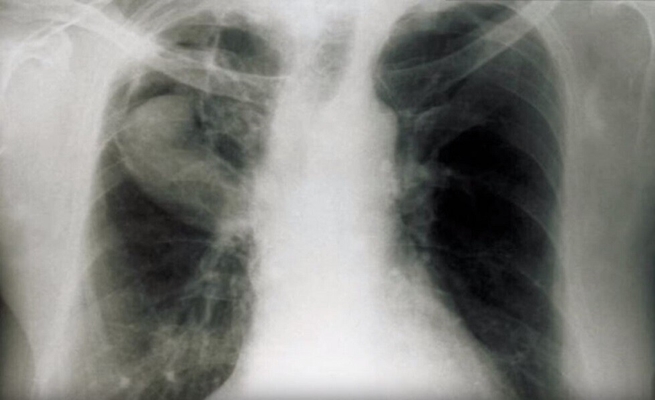

تفيد Fox News، بأن المواطن سكوت دوناهو (49 سنة) بدأ في شهر مارس الماضي يعاني من نوبات سعال شديد، أصبحت لاحقا تنتهي بالتقيؤ، اعتقد الأطباء في البداية أنه مصاب بالتهاب رئوي ووصفوا له مضادات حيوية، ولكن حالة الرجل الصحية ساءت أكثر، حتى أن أحد أبنائه اضطر إلى استدعاء سيارة الإسعاف.

شخص الأطباء في المستشفى إصابة الرجل بمرض “الفطار البرعمي” الذي يسببه نوع من الفطريات المنتشر في أمريكا الشمالية، حيث يصاحب هذا المرض آلام في العضلات وفقدان الوزن وآلام في الصدر وإرهاق، وكان كلب هذا الرجل قد أصيب بهذه الأعراض عام 2018، وانتهت بالموت.

قضى الرجل ثلاثة أشهر في المستشفى، كان خلالها يتغذى عبر أنبوب وربط ثلاث مرات إلى جهاز التنفس الصناعي، وحينما تم توصيله بجهاز التنفس الصناعي للمرة الثانية طلب من أبنائه أن يجتمع أفراد الأسرة “انتظارا للموت”، على حد تعبيره.